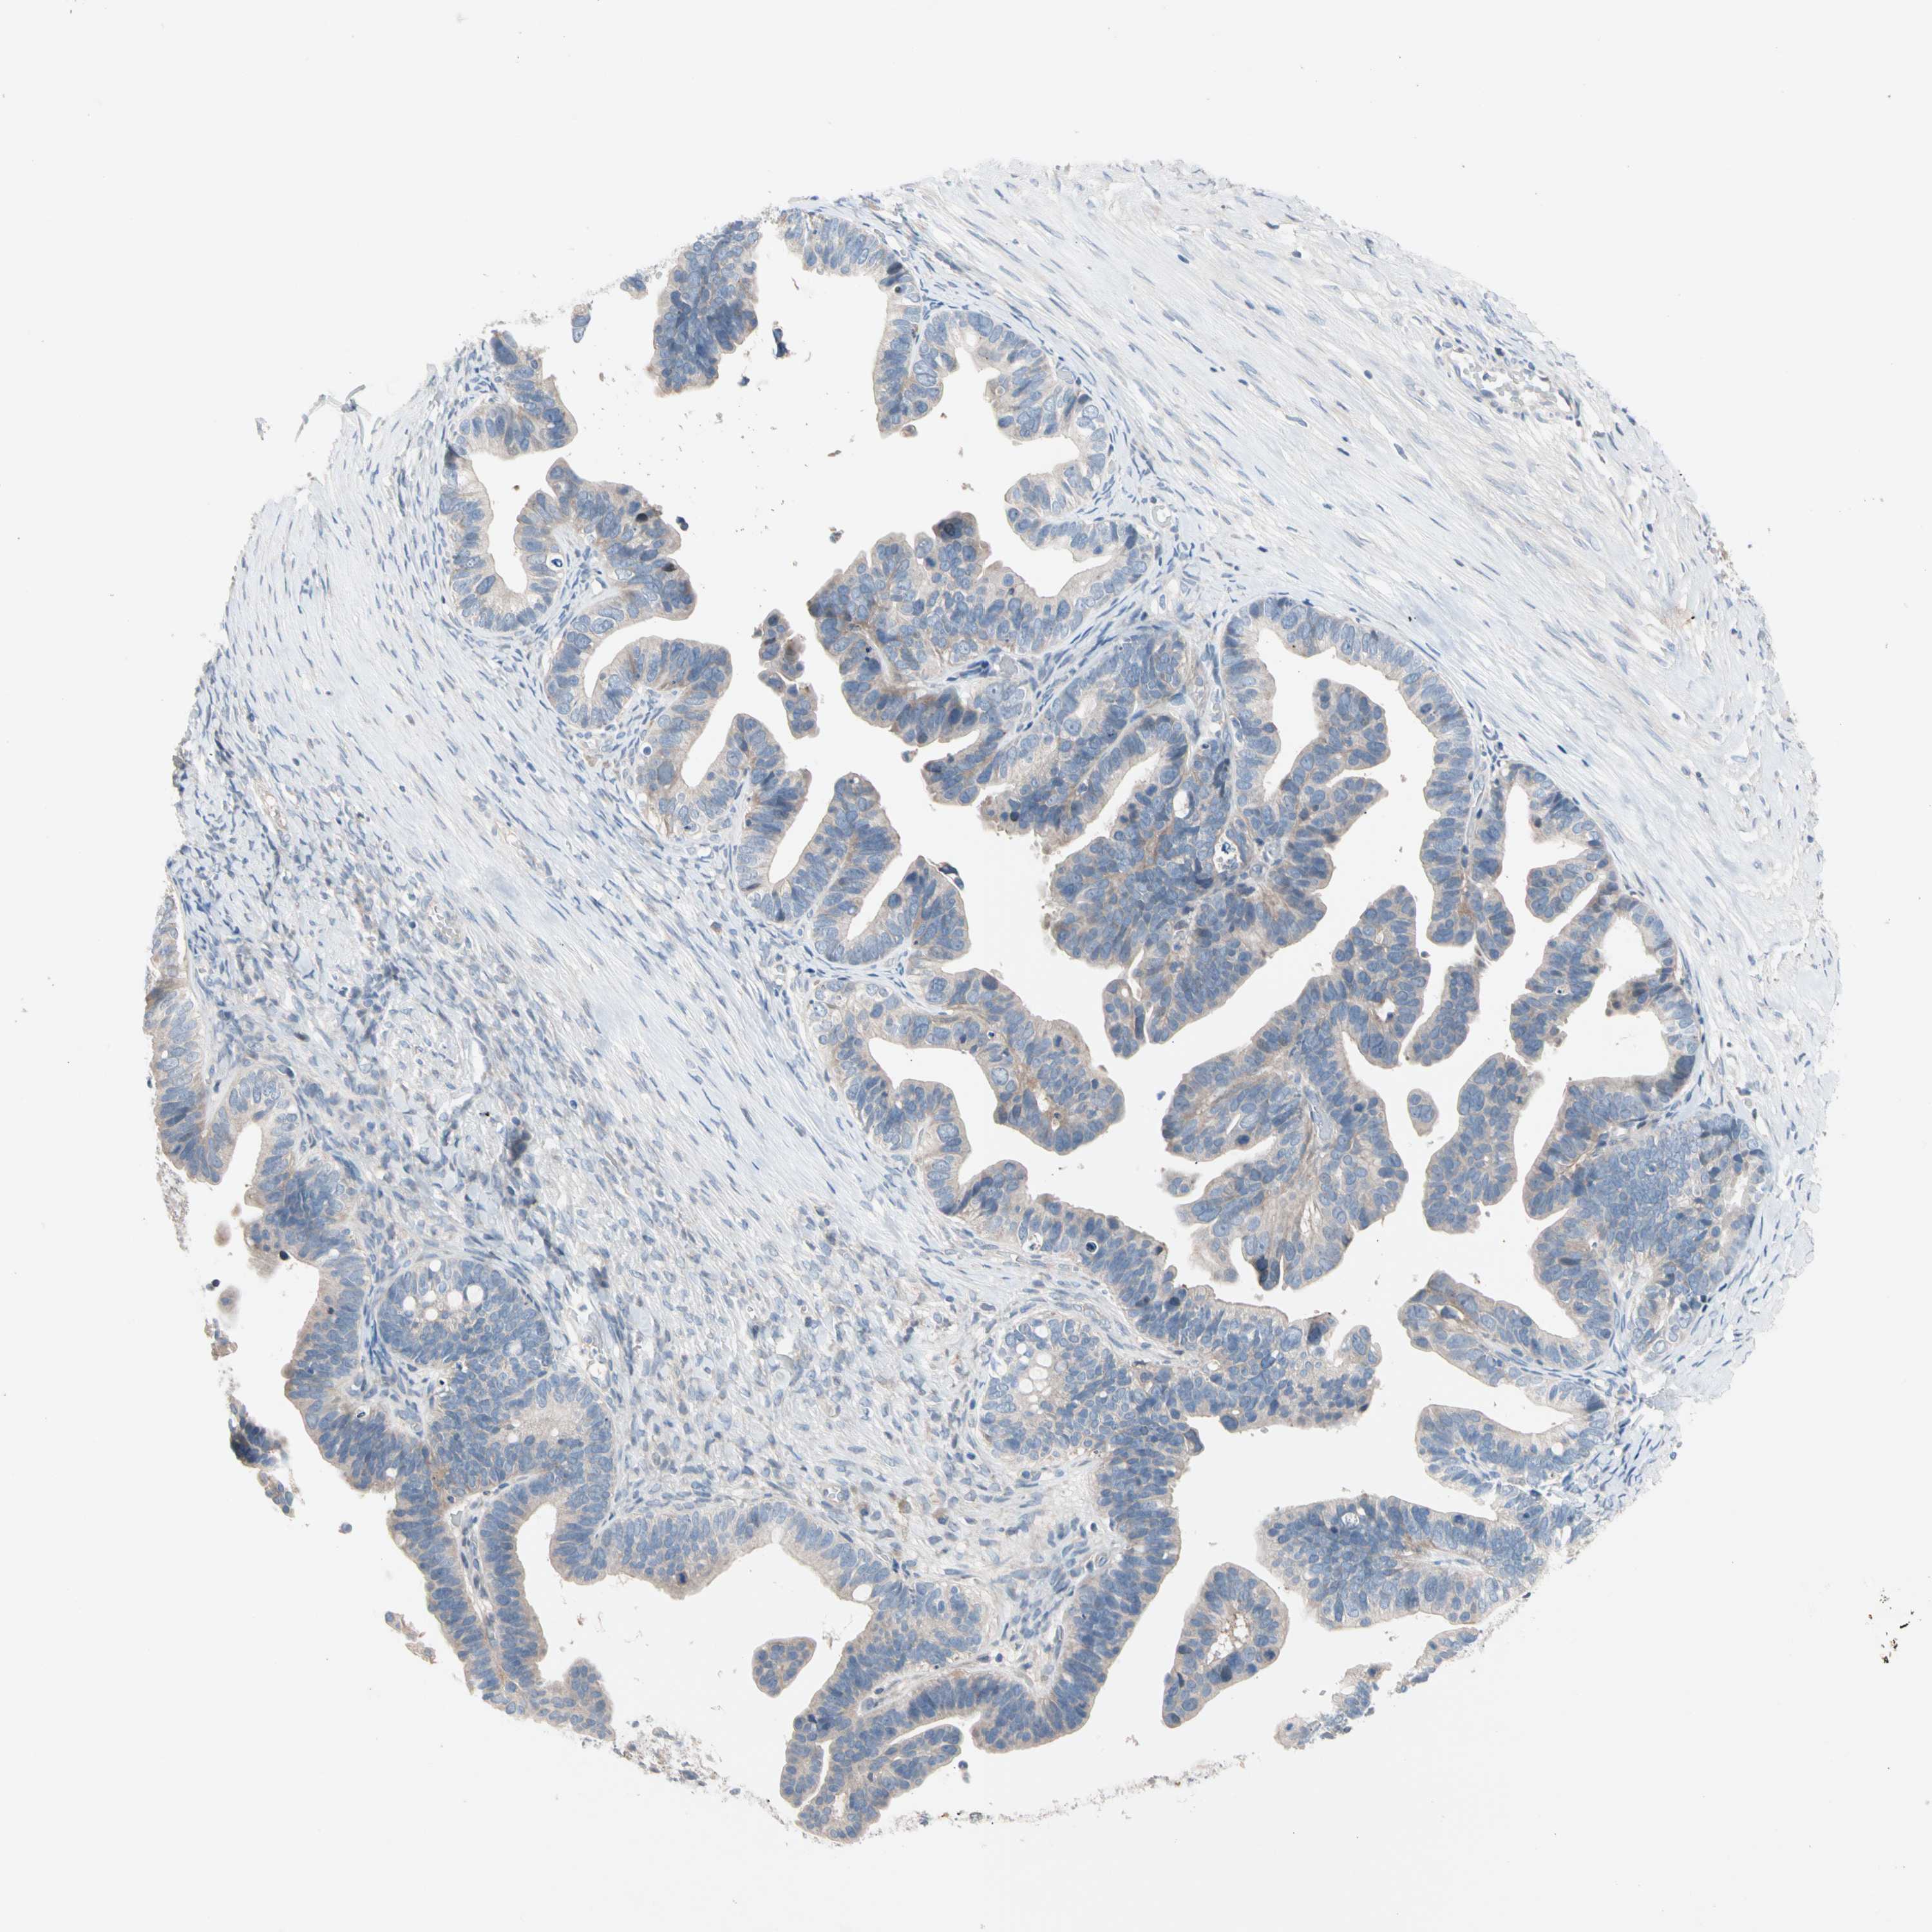

OVARIAN CANCER - Protein expressioni

A mouse-over function shows sample information and annotation data. Click on an image to view it in a full screen mode. Samples can be filtered based on level of antibody staining by selecting one or several of the following categories: high, medium, low and not detected. The assay and annotation is described here.

Note that samples used for immunohistochemistry by the Human Protein Atlas do not correspond to samples in the TCGA dataset.

Antibody stainingi

Antibody staining in the annotated cell types in the current human tissue is reported as not detected, low, medium, or high, based on conventional immunohistochemistry profiling in selected tissues. This score is based on the combination of the staining intensity and fraction of stained cells.

Each image is clickable and will lead to virtual microscopy that enables deeper exploration of all samples and also displays staining intensity scores, fraction scores and subcellular localization as well as patient and tissue information for each sample.

Antibody HPA026823